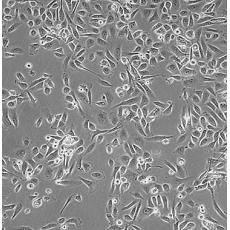

PC-3M

中文名稱 人前列腺癌細胞

組織來源 前列腺癌;骨髓轉移;男性

生長特性 adherent

形態特征 epithelial